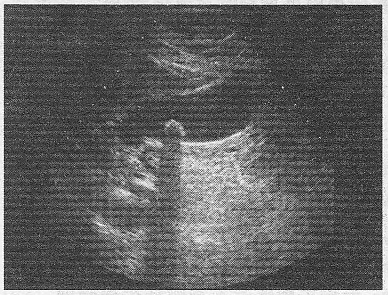

3.如圖,膽囊結(jié)石與膽囊息肉超聲最主要鑒別點(diǎn)是

A.是否有聲影

B.回聲強(qiáng)度

C.是否隨體位改變而移動(dòng)

D.是否有血流

E.體積大小

正確答案:AC 解題思路:膽囊結(jié)石聲像圖顯示①?gòu)?qiáng)光團(tuán);②后伴聲影;③可移動(dòng)。膽囊息肉聲像圖顯示:①?gòu)?qiáng)光團(tuán);②無(wú)聲影;③不移動(dòng)。